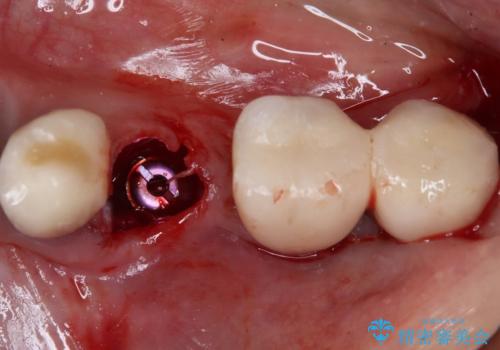

- 下顎前歯が痛んで近医を受診したところ、下顎前歯2本を抜歯してインプラント治療が必要と診断されたとのことで来院された患者様です。

診査の結果、下顎左側中切歯の神経が失活していることが痛みの原因であり、根管治療を行う必要があると診断されました。

根管治療を行った後にオールセラミッククラウンにて補綴することとしました。

隣在歯にも根尖部の炎症が及んでいるように見えましたが、術前診査では神経が失活している様子がなかったため、まずは原因歯から処置を行うこととしました。

初回の根管治療後には痛みが速やかに改善し、6か月後のレントゲン写真では根尖の病変が消失していることが確認できました。